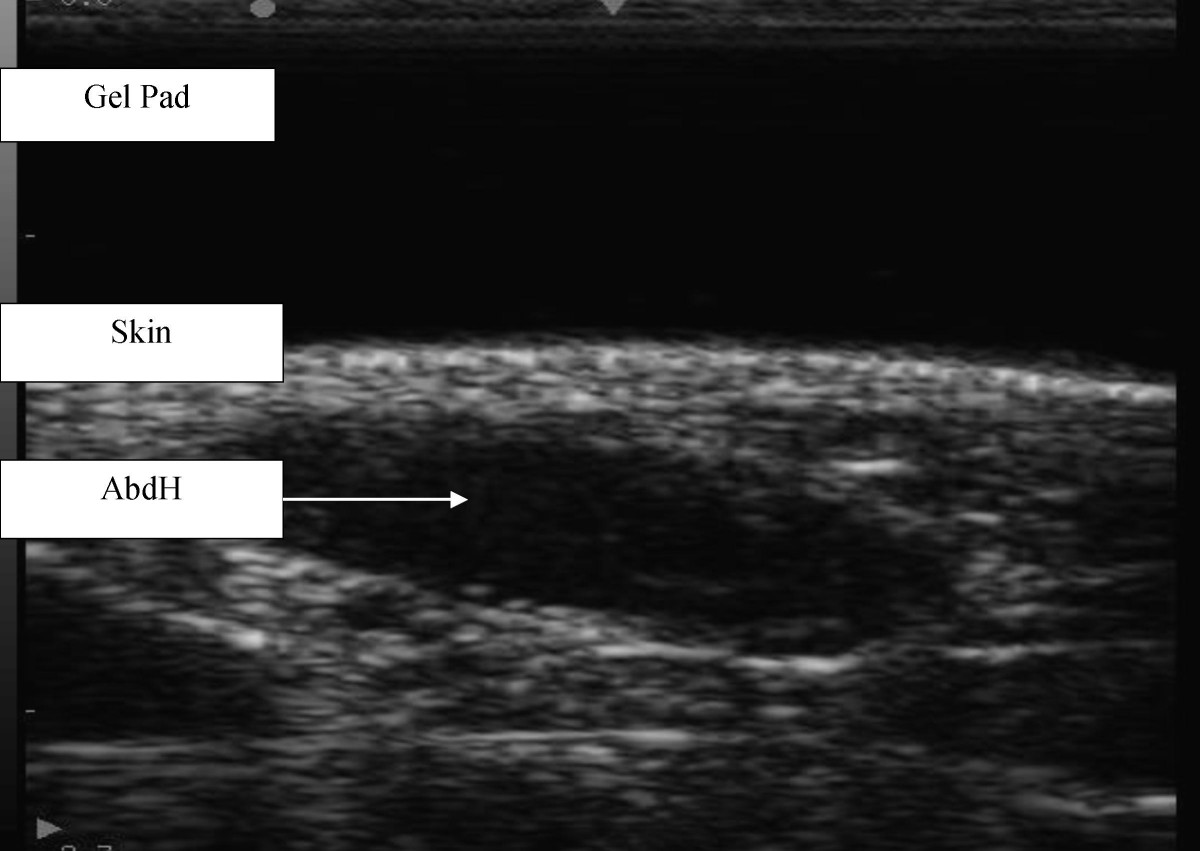

Figure 2

Ultrasound image of abductor hallucis muscle from Chison 8300 (longitudinal view).

Each participant was positioned in supine lying. The heel and plantar aspect, excluding the first metatarsal, of the involved foot rested against a stable platform designed to fix the ankle in a zero degree neutral position. The posterior aspect of the knee was supported in approximately 15-degrees flexion. The uninvolved leg was also supported. The sonographer manually palpated relevant bony anatomical landmarks and marked them for orientation. These included a reference line for scanning directly inferior from the most anterior aspect of the medial malleolus. Scanning occurred with the transducer applied onto the gel pad that lay on the skin overlying the abductor hallucis muscle belly at a perpendicular angle to the aforementioned scanning line and long axis of the foot on the proximal aspect of the reference line to encompass the muscle fibres of abductor hallucis. The abductor hallucis muscle was imaged with the transducer applied at a perpendicular angle to the long axis of the foot on the proximal aspect of the reference line. Minimal pressure was applied with the transducer to reduce any possible alterations to the muscle fibres and architecture. Three separate images of the abductor hallucis muscle were captured using both machines for both left and right feet (Figure 1 &2) and stored on the hard drive for later analysis. Measurement and analysis were undertaken independent of one another to ensure blinding of the results. Blinding was undertaken by identifying and removing all identifiable details such as image number, US machine and patient number and the sonographer randomly evaluated each of the scanned images.

A 'higher end' Philips HD11 ultrasound machine, with linear transducer (12-5 MHz), and a Chison 8300 Deluxe Digital 'portable' ultrasound system, with linear transducer (7.5 MHz) were used to scan images of the abductor hallucis muscle. An Aquaflex® Ultrasound Gel Pad (Fairfield, USA) was applied directly onto the participant's skin, over the abductor hallucis muscle, ensuring optimal transducer contact and signal penetration. Philips Q-lab Software (Release 5.0) was employed for data quantification from the images taken from the Philips HD11, and the Chison 8300 inbuilt software was used for the images captured on that machine.